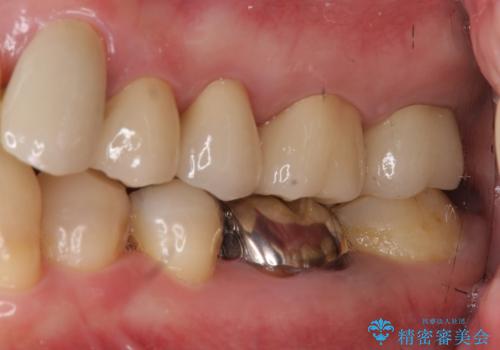

奥歯の被せ物のやり直し 精密根管治療

オールジルコニアクラウンに変え、審美的な被せ物になりました。

- 約70万円 内訳:ジルコニアクラウン10万円x4、TeC 1万円x4 根管治療15万円、ファイバーコア2万円費用は治療当時の料金となります